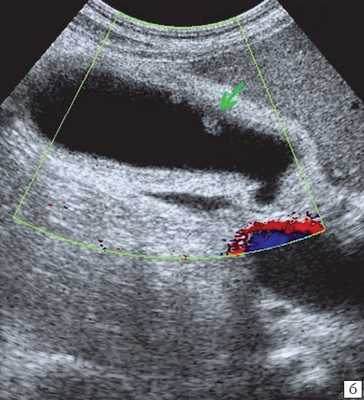

(Левый) На поперечном УЗ срезе определяется сладж, заполняющий желчный пузырь. Сладж имеет такую же эхогенность, как и печень, это состояние называют «гепатизацией».

(Правый) Положение пациента на левом боку. На продольном УЗ срезе визуализируется смещающийся книзу под действием гравитации сладж, напоминающий полип. Стенка желчного пузыря не изменена.